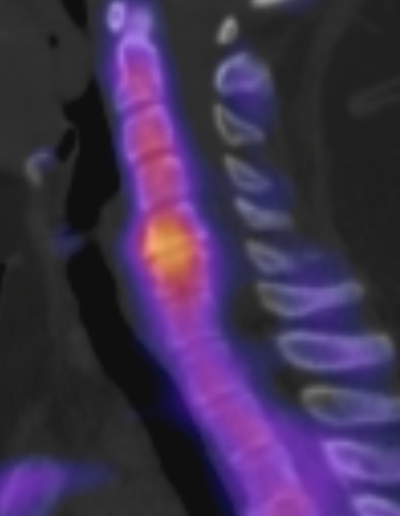

SPECT/CT HWS Osteochondrose

SPECT/CT der Halswirbelsäule mit einer aktivierten Osteochondrose im Segment HWK5/6.